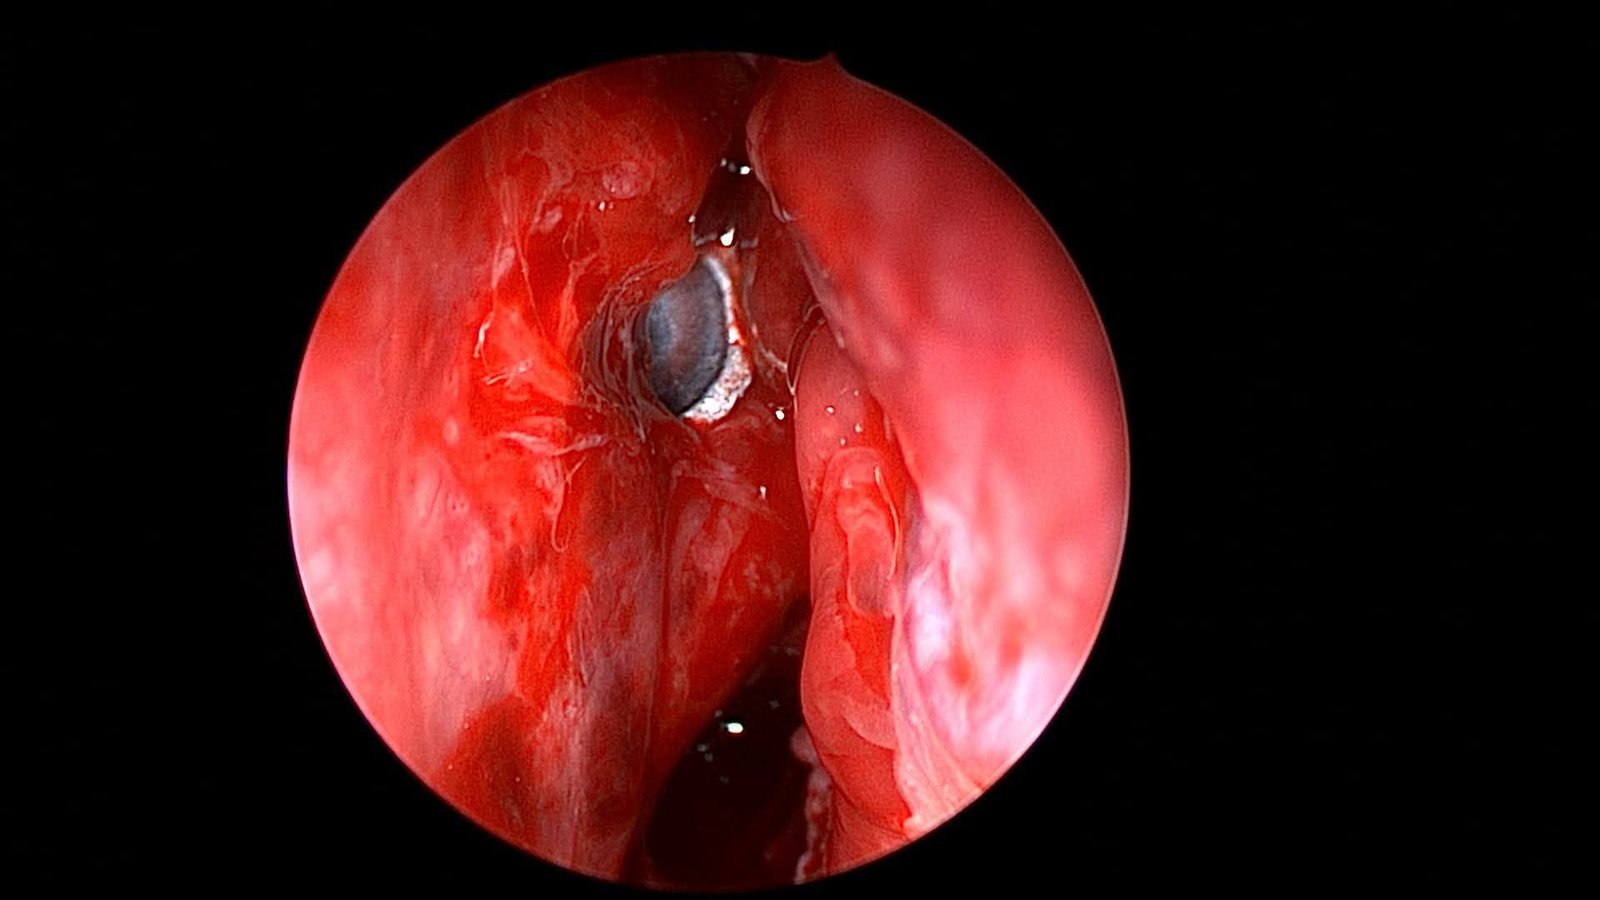

وعلى إثر ذلك، تم التعامل مع الحالة بشكل عاجل، حيث جرى إدخالها إلى عمليات قسم الأنف والأذن والحنجرة، وتمكن الدكتور علاء عبدالسميع، أستاذ مساعد الأنف والأذن والحنجرة، بمشاركة الفريق الطبي المعاون من أطباء وتمريض العمليات، من استخراج الطلقة بنجاح باستخدام منظار الجيوب الأنفية، دون حدوث أي مضاعفات.